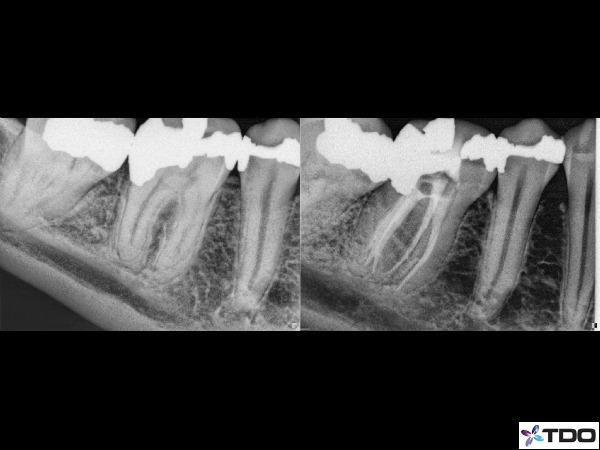

Figure 3: Here is another case from Adam Monroe in which more time and another appointment he was able to find 3 distal canals. It would be very difficult to perform this type of careful work in one appointment.